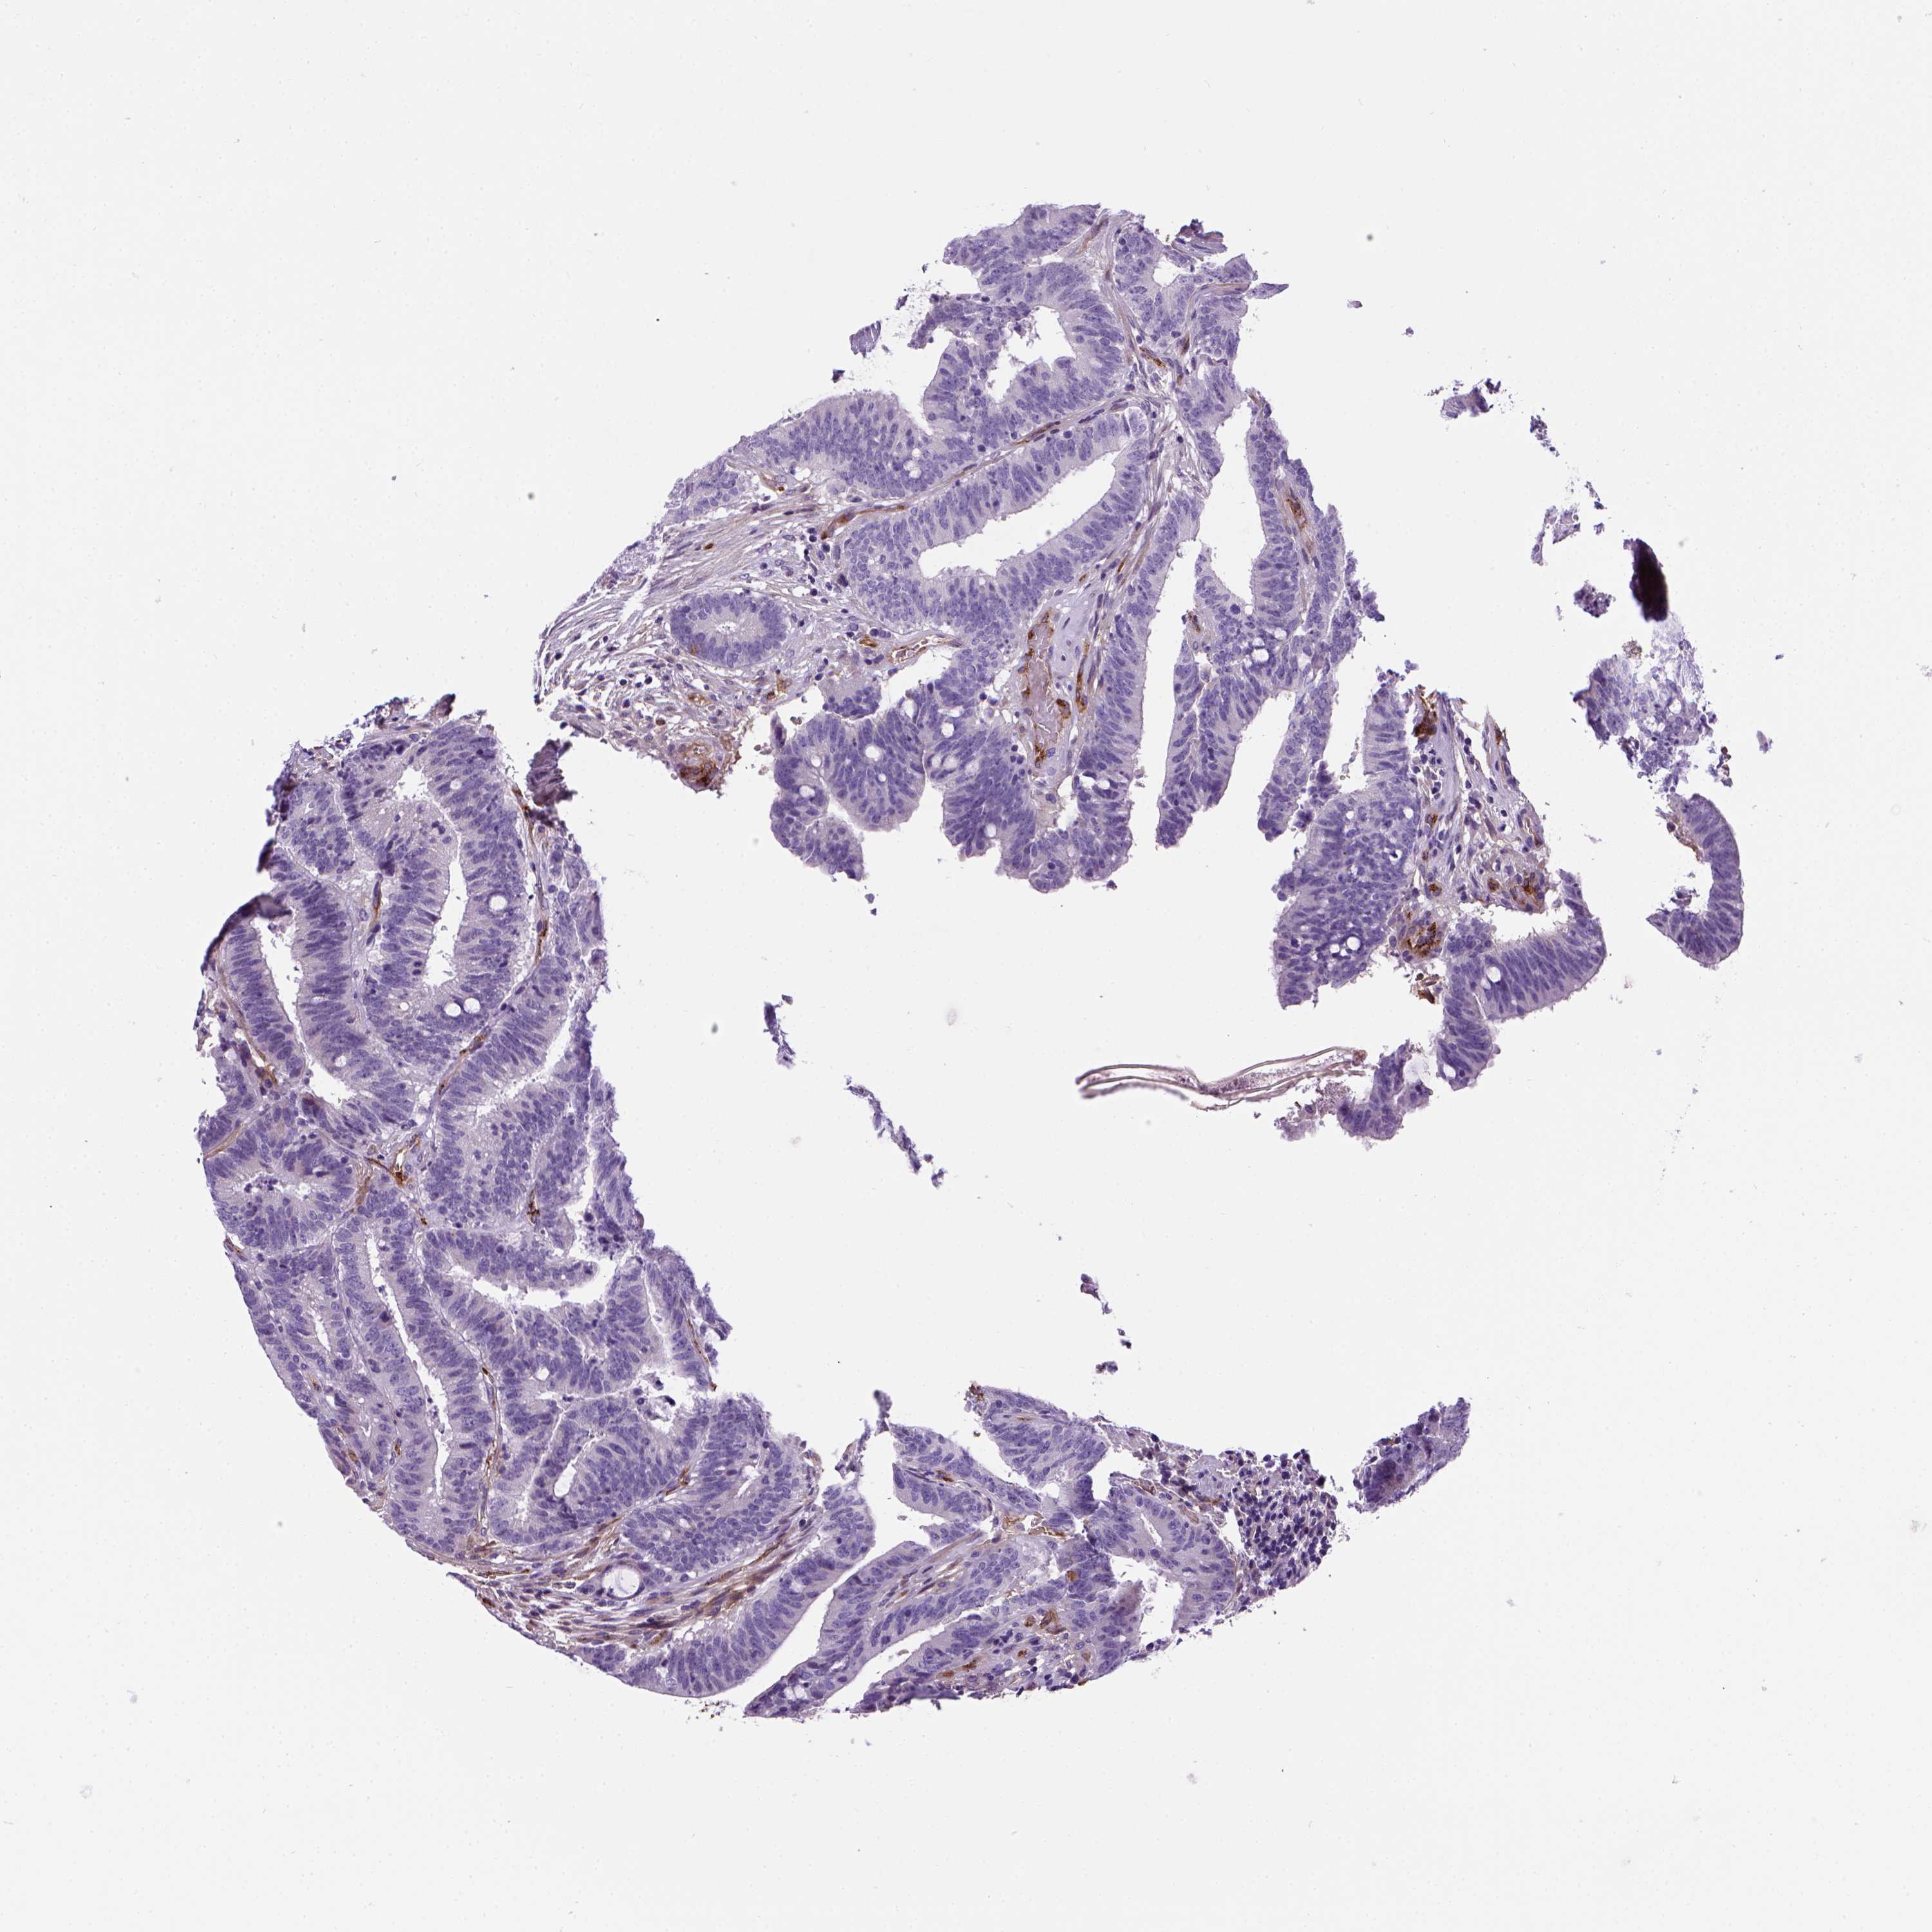

CANCER COLORECTAL CANCER Show tissue menu

COAD TCGA COAD VALIDATION READ TCGA READ VALIDATION PROTEIN COAD CPTAC PROTEIN EXPRESSION

ANTIBODIES

AND

VALIDATION